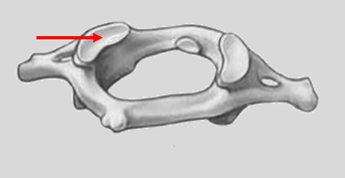

Q1. The highlighted structure in the provided image articulates with which bone?

- Occipital bone

- Temporal bone

- Axis

- Sphenoid bone

Answer – A